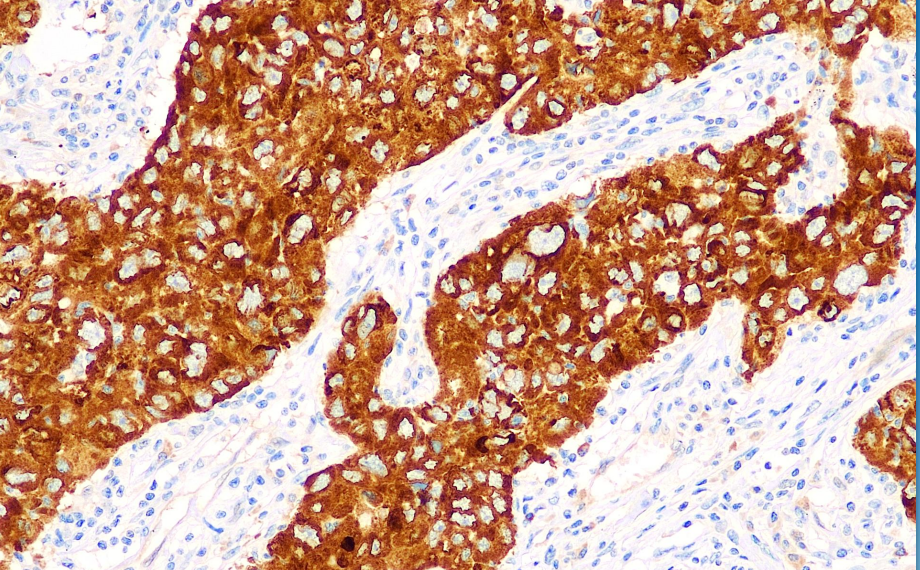

Positive control: Lung adenocarcinoma/cervical squamous carcinoma

insulin-like growth factor II mRNA-binding protein 3 (IMP3) regulates the transcription of insulin-like growth factor during embryo formation It is expressed in some tumor cells such as lung squamous cell carcinoma, lung adenocarcinoma and pancreatic cancer, while its expression in normal tissues (except the gonads) can be ignored. In addition, IMP3 is expressed in melanoma, mesothelioma, epithelial carcinoma and soft tissue sarcoma originating from the bladder, cervix, colon, esophagus and stomach. At the same time, it can be used as a prognostic reference for renal cell carcinoma. The 5-year survival period of IMP3-positive renal cell carcinoma is much shorter than that of IMP3-negative renal cell carcinoma. It is worth noting that IMP3 can serve as an extremely important prognostic reference for invasive cervical squamous cell carcinoma. It is hardly expressed in CINI and CINII lesions, but has a very high positive rate in invasive cervical squamous cell carcinoma.

IMP3 antibody reagents can specifically bind to IMP3 molecular antigens. Immunohistochemical kits containing IMP3 antibody reagents are suitable for prognosis assessment of highly invasive tumors (such as pancreatic cancer, renal cell carcinoma, and ovarian cancer).